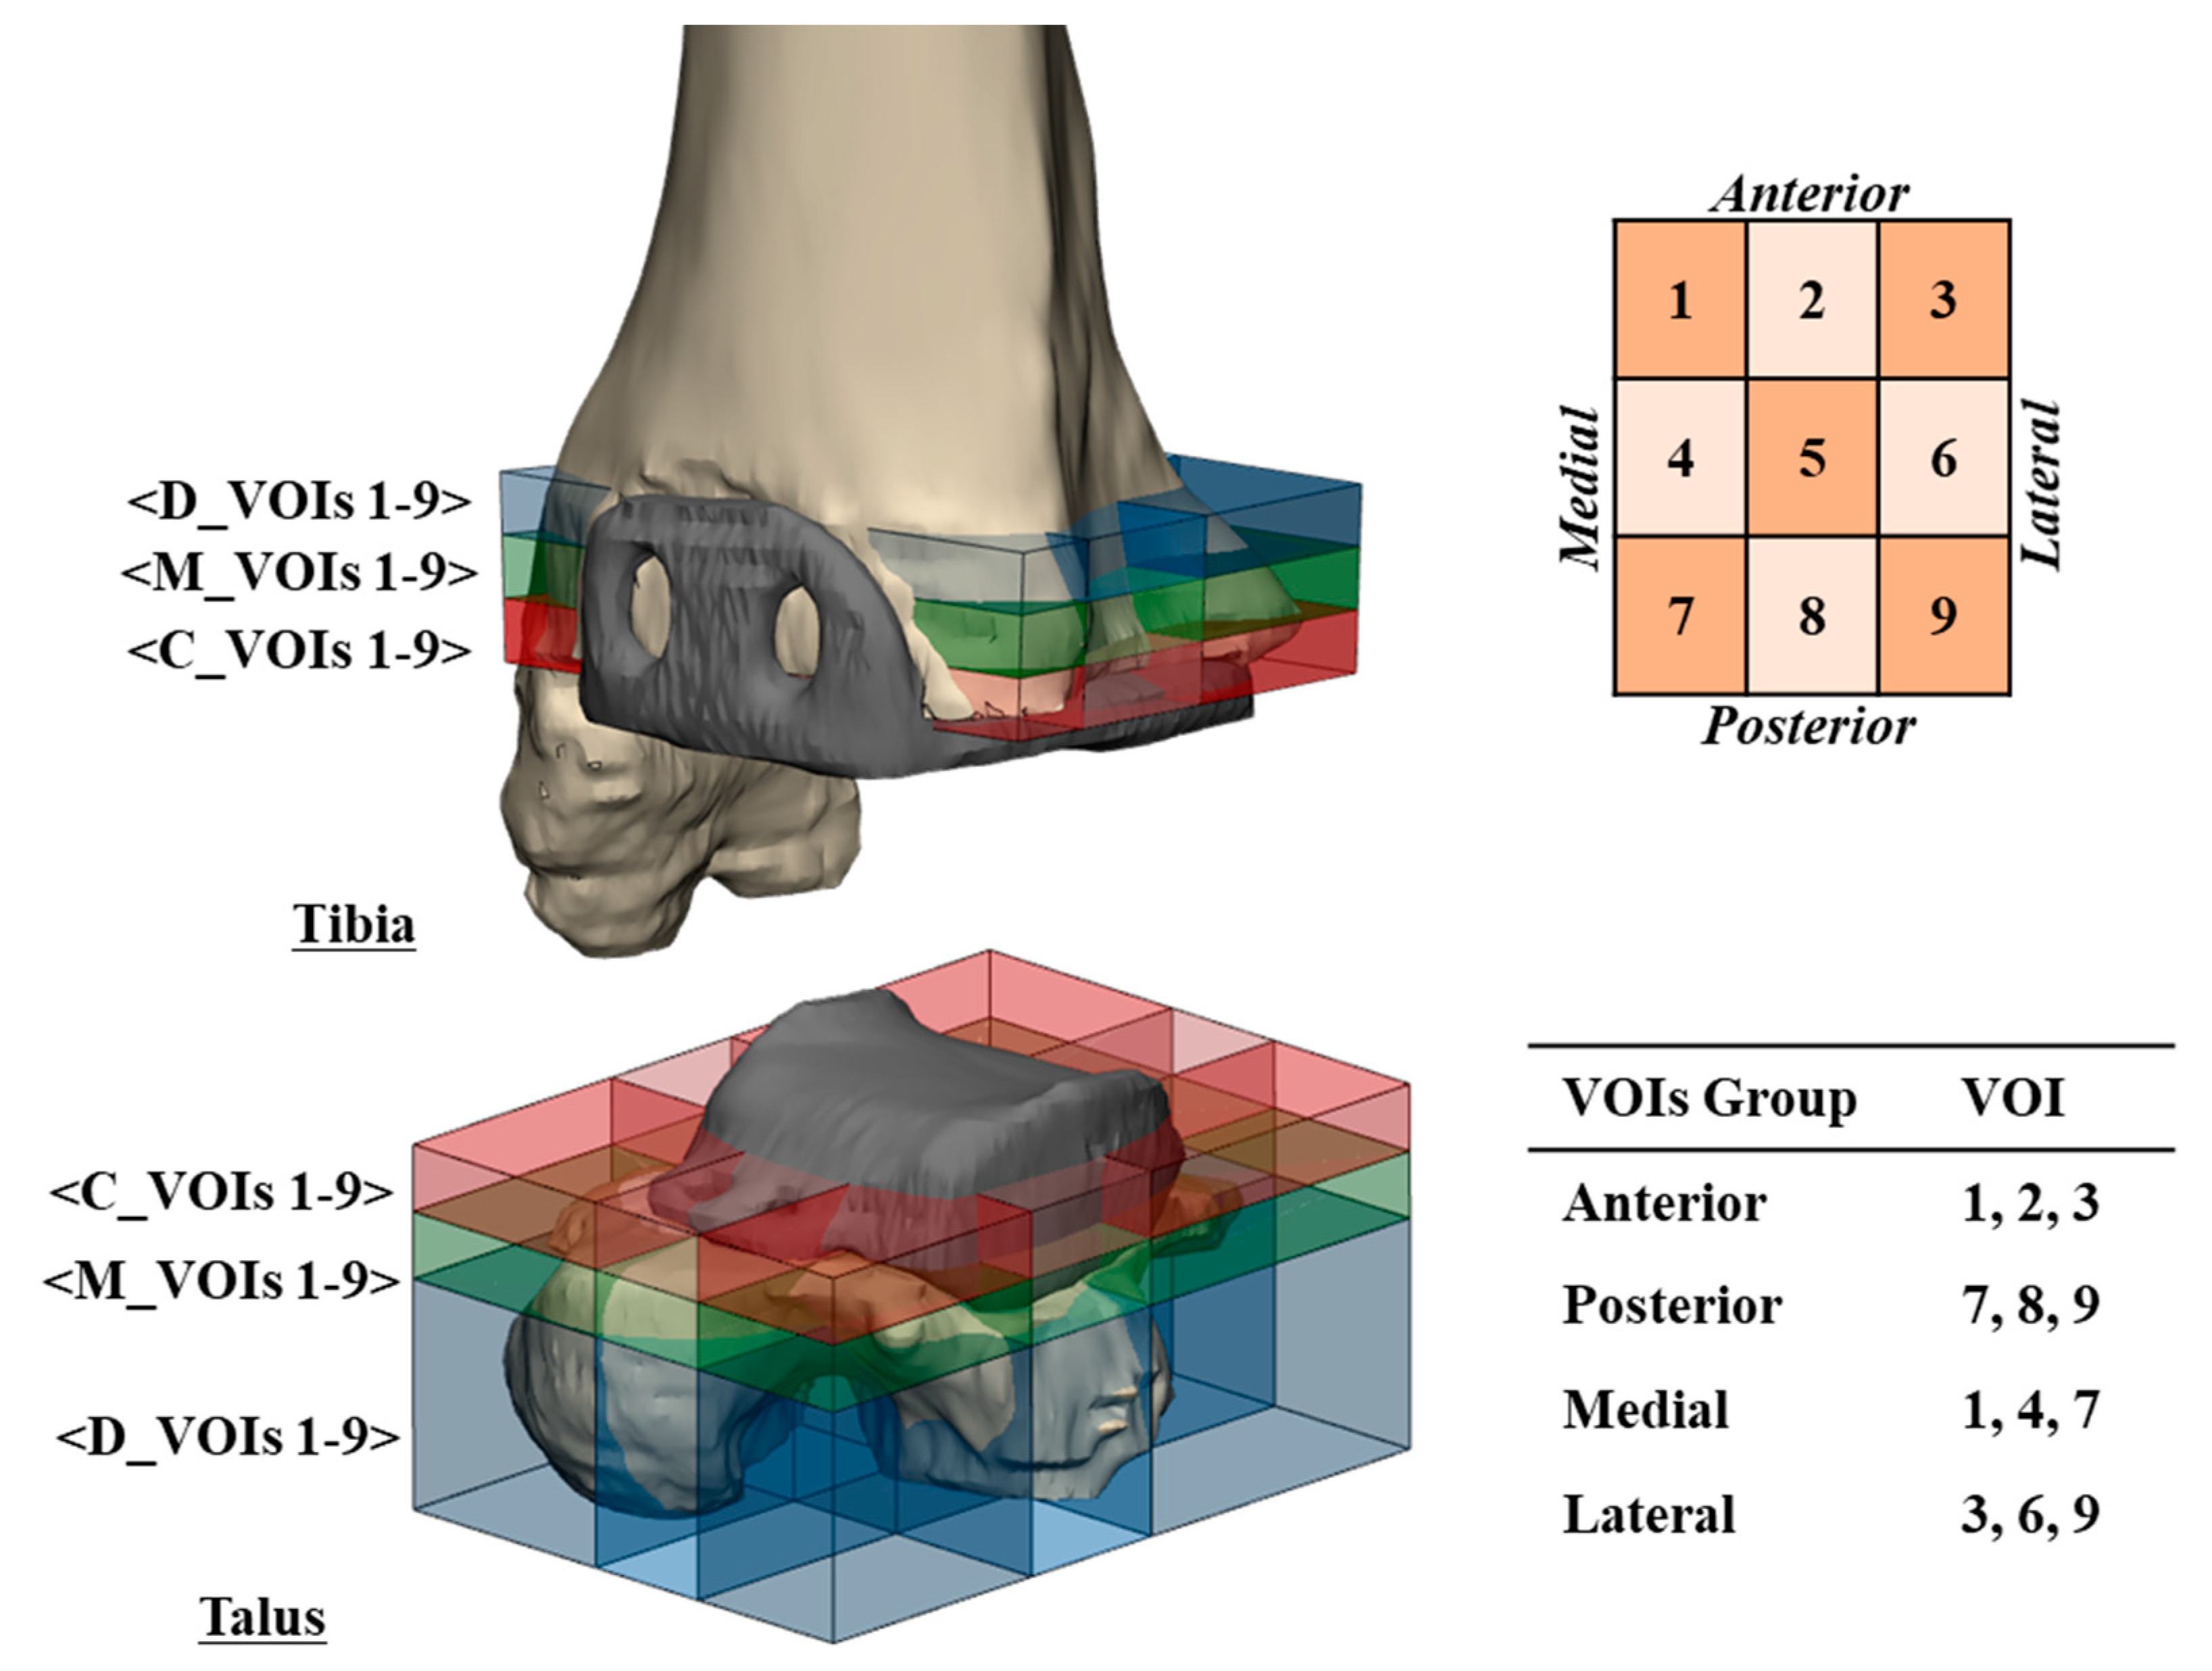

2.3. Measure of Location, Distribution, and Normalized Volume of Osteolysis